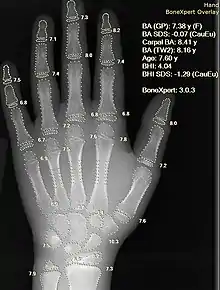

Les réseaux de neurones artificiels sont utilisés comme systèmes de soutien à la décision clinique pour le diagnostic médical, comme dans la technologie Concept Processing dans le logiciel EMR.

- interprétation assistée par ordinateur d'images médicales. De tels systèmes aident à numériser des images numériques, par exemple de la tomodensitométrie, pour des apparences typiques et pour mettre en évidence des coupes ostentatoires, telles que des maladies possibles. Une application typique est la détection d'une tumeur ;